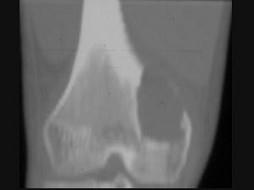

问题 男,22岁,左侧膝部肿胀,疼痛2个月余,请结合影像学检查,选出最可能的诊断 ( )

选项 A、动脉瘤样骨囊肿 B、软骨肉瘤 C、骨肉瘤 D、骨髓炎 E、骨脓肿

答案 A